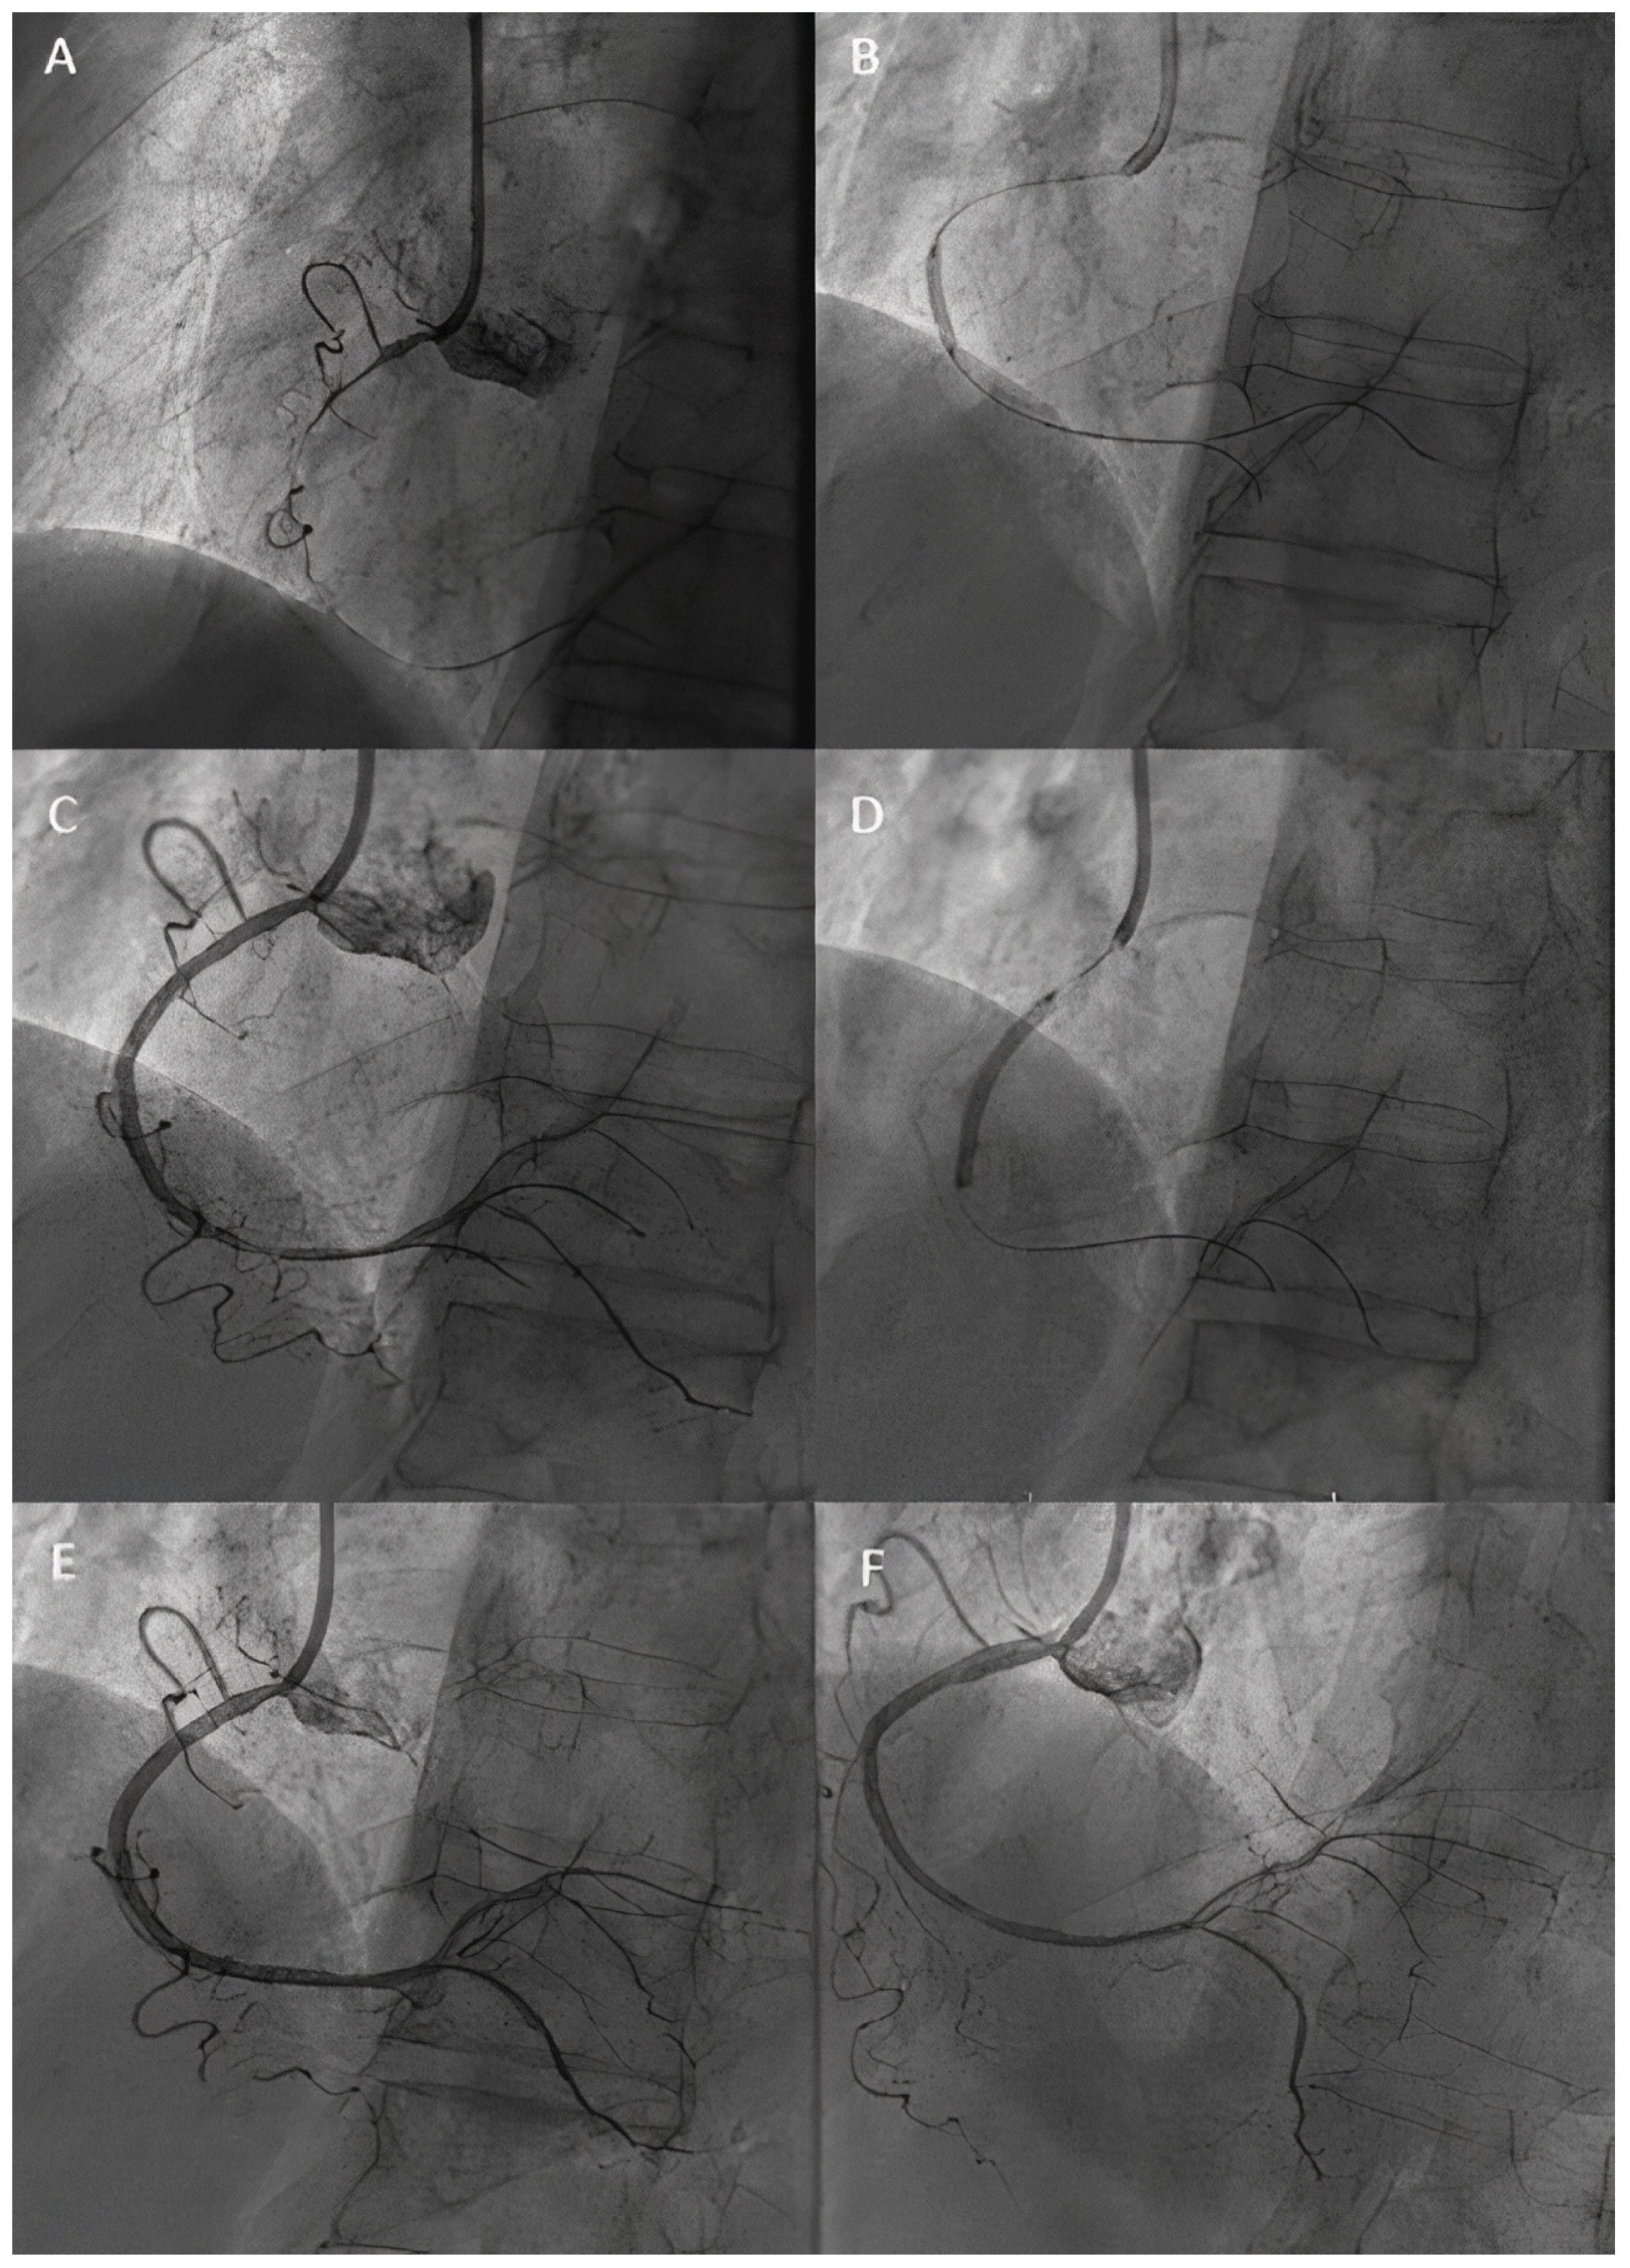

- Erdoğan, E.; Li, Z.; Zhu, Y.X.; Tufaro, V.; Feng, S.L.; Li, Q.; Liang, L.; Chang, S.; Bu, L.T.; Liu, B.; et al. DCB combined with provisional DES implantation in the treatment of De Novo Medina 0,1,0 or 0,0,1 left main coronary bifurcation lesions: A proof-of-concept study. Anatol. J. Cardiol. 2022, 26, 218–225. [Google Scholar] [CrossRef] [PubMed]